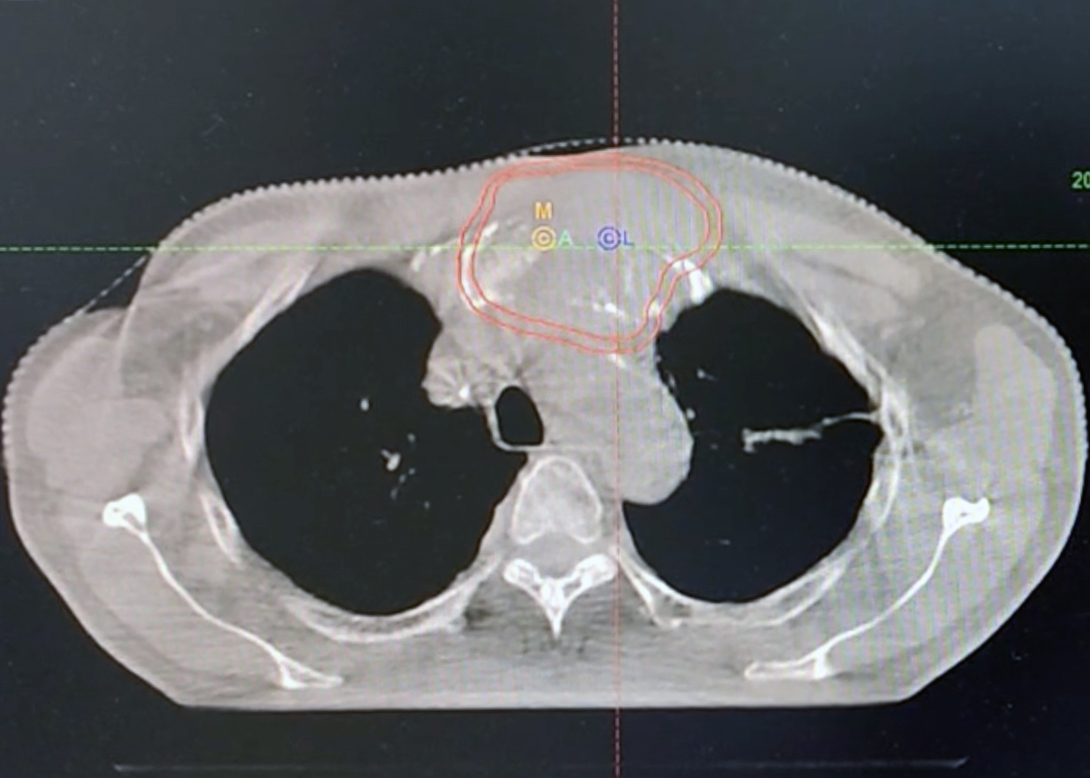

刘先领院长精准提出两步走策略:一方面,为尽快控制局部病情,在等待“泛癌种NGS检测”结果期间,先行对胸骨转移瘤进行放射治疗;另一方面,计划在此后进行穿刺,联合病理科开展更为精细的免疫组化分析。

随后的诊疗进程验证了这一思路的高效性,放疗及时稳定了局部病情,而进一步的病理检测带来了关键发现:患者PD-L1表达呈极高水平(CPS评分90)。

鉴于原发灶仍不明确,刘先领院长果断决定选择“白蛋白紫杉醇”这一兼具广谱抗肿瘤活性(对肺癌、胃癌等多种实体瘤有效)且耐受性较好的化疗药物,联合卡铂及免疫抑制剂进行综合治疗。方案实施后疗效显著,患者的胸骨肿物明显缩小,困扰多时的胸痛等症状大幅缓解,全身状况显著改善,食欲与精神状态好转。